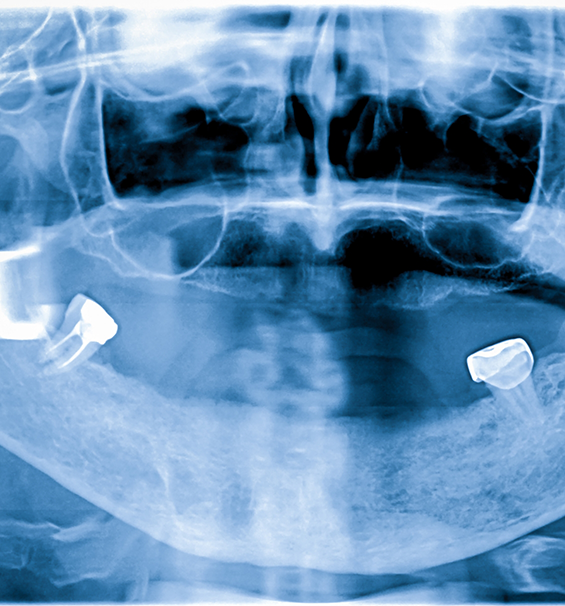

Dental Implants

Dental implants are often referred to as the gold standard when it comes to replacing missing teeth, and the reason is simple—they offer so much more than traditional restoration solutions. The process involves titanium posts that are placed directly into the jawbone, where they fuse and become replacement tooth roots. From there, custom-made restorations are attached and receive impressive support. Dental implants can prevent the bone loss in the jaw that is associated with lost teeth, and with the right care, they can last for decades.